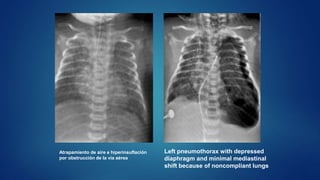

Atrapamiento de aire e hiperinsuflación

por obstrucción de la via aérea

Left pneumothorax with depressed

diaphragm and minimal mediastinal

shift because of noncompliant lungs